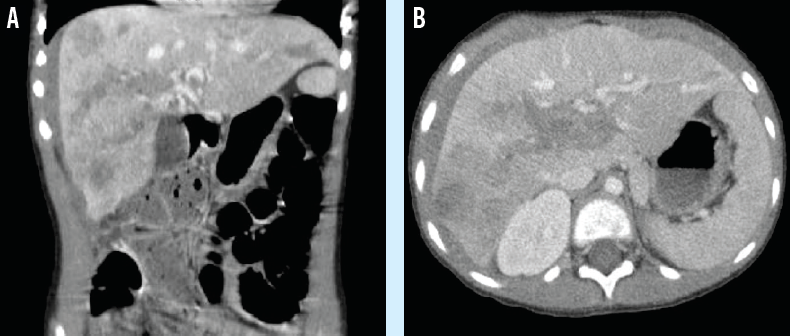

ewing sarcoma

Jennifer L. Weiner, MS, CPNP; Pamela L. Horn, MS, CNP, RNFA, MSN, CRNP; Thomas J. Scharschmidt, MD; Nicholas D. Yeager, MD

Ewing sarcoma is a rare and aggressive childhood cancer that generally is diagnosed in adolescents.